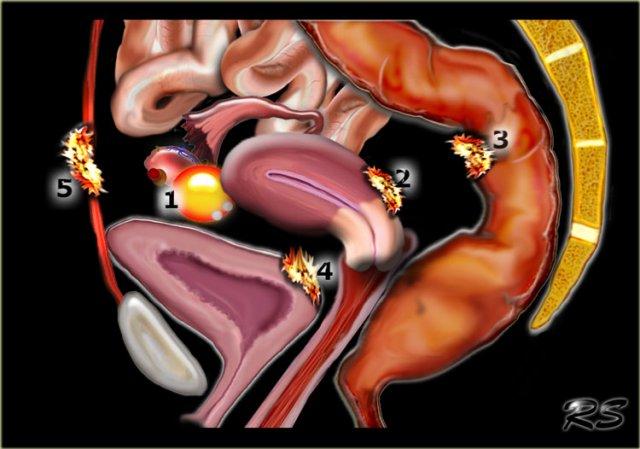

Hình minh họa cho thấy các vị trí điển hình của lạc nội mạc tử cung:

- Lạc nội mạc tử cung dạng u nang buồng trứng (endometrioma)

- Lạc nội mạc tử cung sau cổ tử cung

- Lạc nội mạc tử cung xâm lấn sâu vào ruột

- Lạc nội mạc tử cung tại bàng quang

- Lạc nội mạc tử cung tại thành bụng